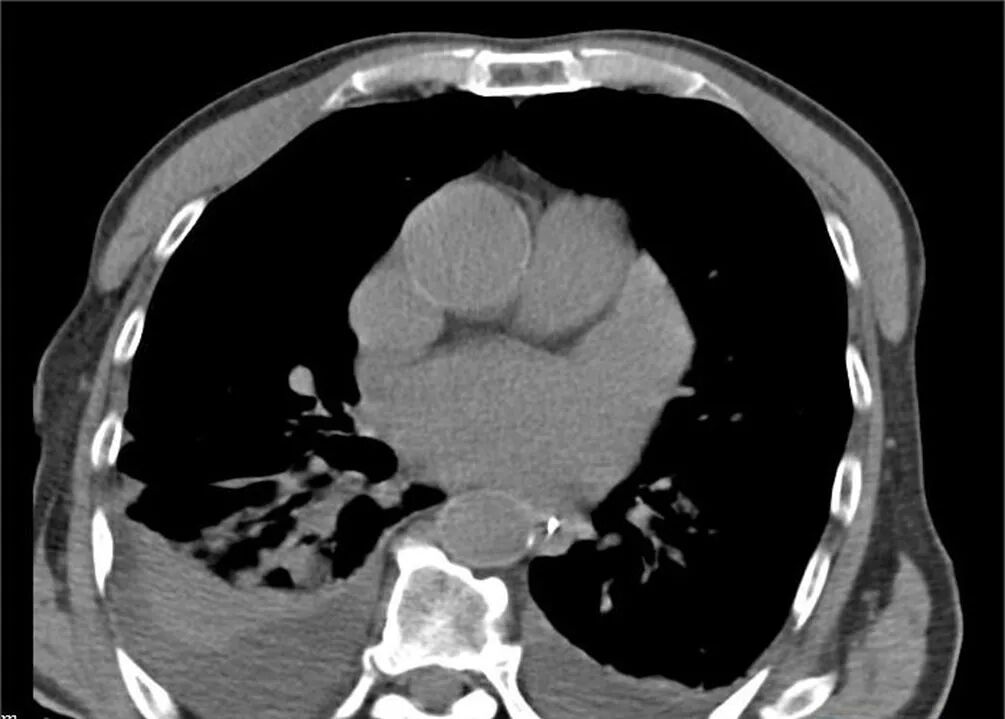

患者的胸部CT影像学资料

纵隔窗:双侧少量胸腔积液